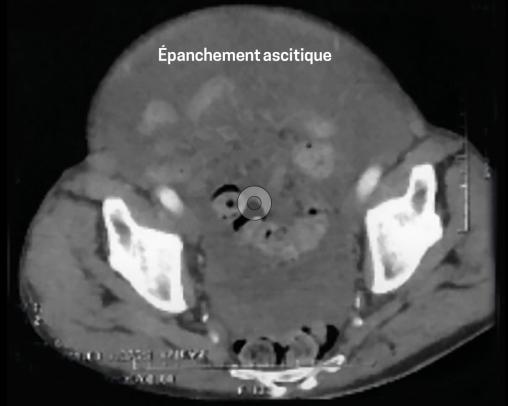

Le scanner abdominal (fig. 1 et 2)montre un volumineux épanchement ascitique diffus, un foie dysmorphique. Le bilan d’hépatopathie est négatif. L’ACE est élevé (8,79 µg/L), comme le CA 19,9 (57 UI/mL).